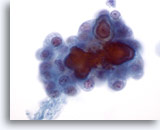

Onbepaalbaar voor maligniteit

Deze catergorie omvat in ons lab ook monsters waarvan de voorspellende waarde van maligniteit bij histologie minder dan 50% is (meestal minder dan 30%) en hoger dan 10%.[6, 7] Dit omvat die monsters die een paar kenmerken vertonen van papillair carcinoom, maar die onvoldoende zijn voor een diagnose. [7] De positieve voorspellende waarde hiervan varieert in de literatuur van 20 tot 54%. [7, 9, 10, 11] Deze laesies vertegenwoordigen vaak de folliculaire variant van papillair carcinoom. In deze diagnostische categorie vallen ook folliculaire en Hürthle celneoplasma’s, die worden gekenmerkt door weinig colloïde en folliculaire cellen in microfollikels en opeengepakte groepen of losse Hürthle-cellen. De positieve voorspellende waarde van deze laesies voor een carcinoom varieerde in de literatuur van 2 tot 91%,[6, 9, 10, 12, 13, 14, 15, 16, 17, 18, 19, 20, 21, 22, 23, 24, 25, 26, 27]waarschijnlijk als gevolg van verschillende definities van deze termen en wisselende criteria die worden gebruikt voor het schema en bij de histologische diagnose. Bij de meeste rapporten is deze waarde minder dan 30%. [10, 15, 22, 24, 27]